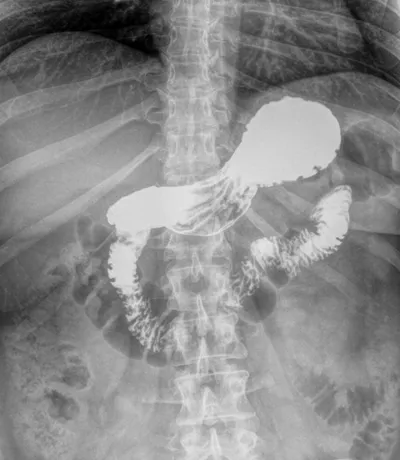

Un transit baryté est un examen radiologique permettant d'étudier le tube digestif haut : œsophage, estomac, duodénum et intestin grêle. Il consiste à faire ingérer par un patient de la baryte, un produit de contraste opaque aux rayons X.

Des clichés radiographiques sont pris à différents temps, permettant d'explorer l'ensemble du tractus digestif haut à mesure que celui-ci se remplit de baryte.

Cet examen permet de détecter des anomalies telles que des tumeurs, polypes, diverticules, inflammations et infections.